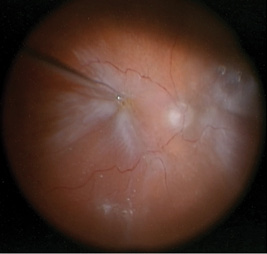

Four weeks later, the patient presented with a sudden curtain across his vision in his right eye, and visual acuity had decreased to hand motions. On examination, he had a starfold temporally with a stretch hole at 9:30, and the retina was detached through the macula (Figure 1). He had a prior buckle in place following the GRT repair. Therefore, we planned a vitrectomy with a membrane peel, laser, and tamponade to be determined.

Figure 1. Intraoperative image of the initial presentation of the right eye demonstrating a retinal detachment with a dense epiretinal membrane.